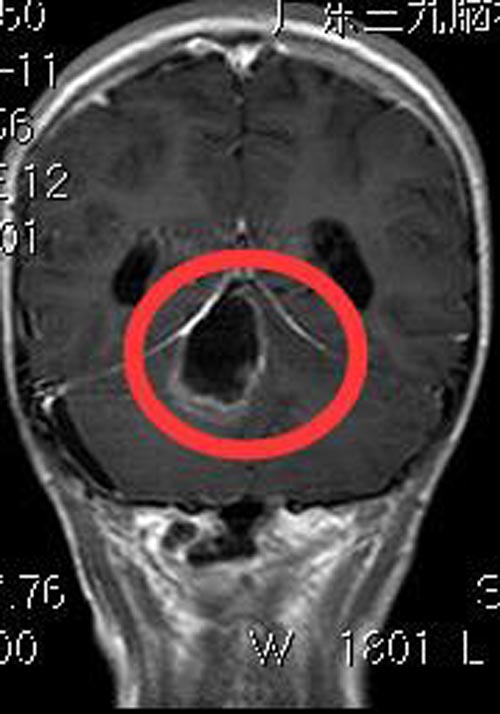

完善术前检查后,由综合神经外科鲁明主任主刀,在全麻下行小脑上蚓部肿瘤切除术,术中见皮层下灰白色肿瘤组织,质软,血供一般,边界较清,荧光显微镜下完整切除肿瘤。术后依依神志清醒,出院时头痛呕吐症状消失,无癫痫发作。术后病理结果:毛细胞星形细胞瘤,WHO I级。